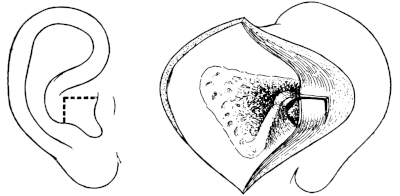

| 186. | Anatomical Preparation of the Middle Ear | 335 |

| 228. | Post-meatal Skin Flaps | 401 |

| 229. | Post-meatal Skin Flaps | 401 |

| 230. | Closure of Wound after ‘Radical’ Mastoid Operation | 401 |

| 231. | Körner’s Post-meatal Flap | 402 |

| 232. | Panse’s Post-meatal Flap | 402 |

| 233. | Stacke’s Post-meatal Flap | 402 |